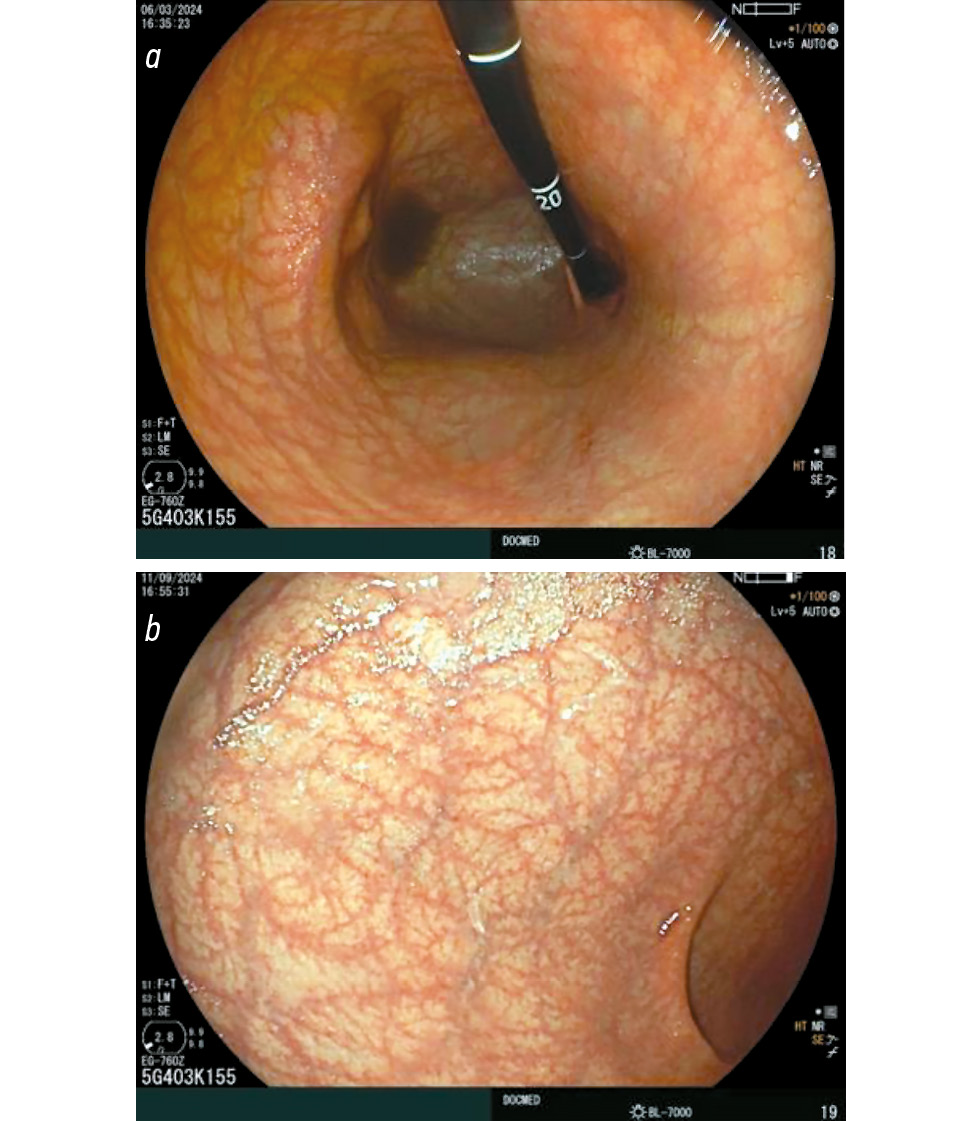

A well-known endoscopic feature of autoimmune gastritis is the reverse atrophy sign, which serves as a key indicator of the disease. In a multicenter study by Krasinskas et al., this sign was detected in 90.1% of patients in Japan [41]. Other endoscopic findings commonly observed in autoimmune gastritis are illustrated in Fig. 2.

Fig. 2. Endoscopic view of “reverse” atrophy. Atrophic changes mucosa of the body of the stomach with preserved mucosa of the antral section. © Eco-Vector, 2025.

A characteristic feature of autoimmune gastritis is the presence of patches of preserved acid-producing mucosa [41]. Terao et al. described this phenomenon as pseudopolyps against the background of diffuse gastric body atrophy, observed in 31.5% of cases (Fig. 3) [27].

Fig. 3. Endoscopic view of preserved acid-producing areas of the gastric body mucosa. © Eco-Vector, 2025.